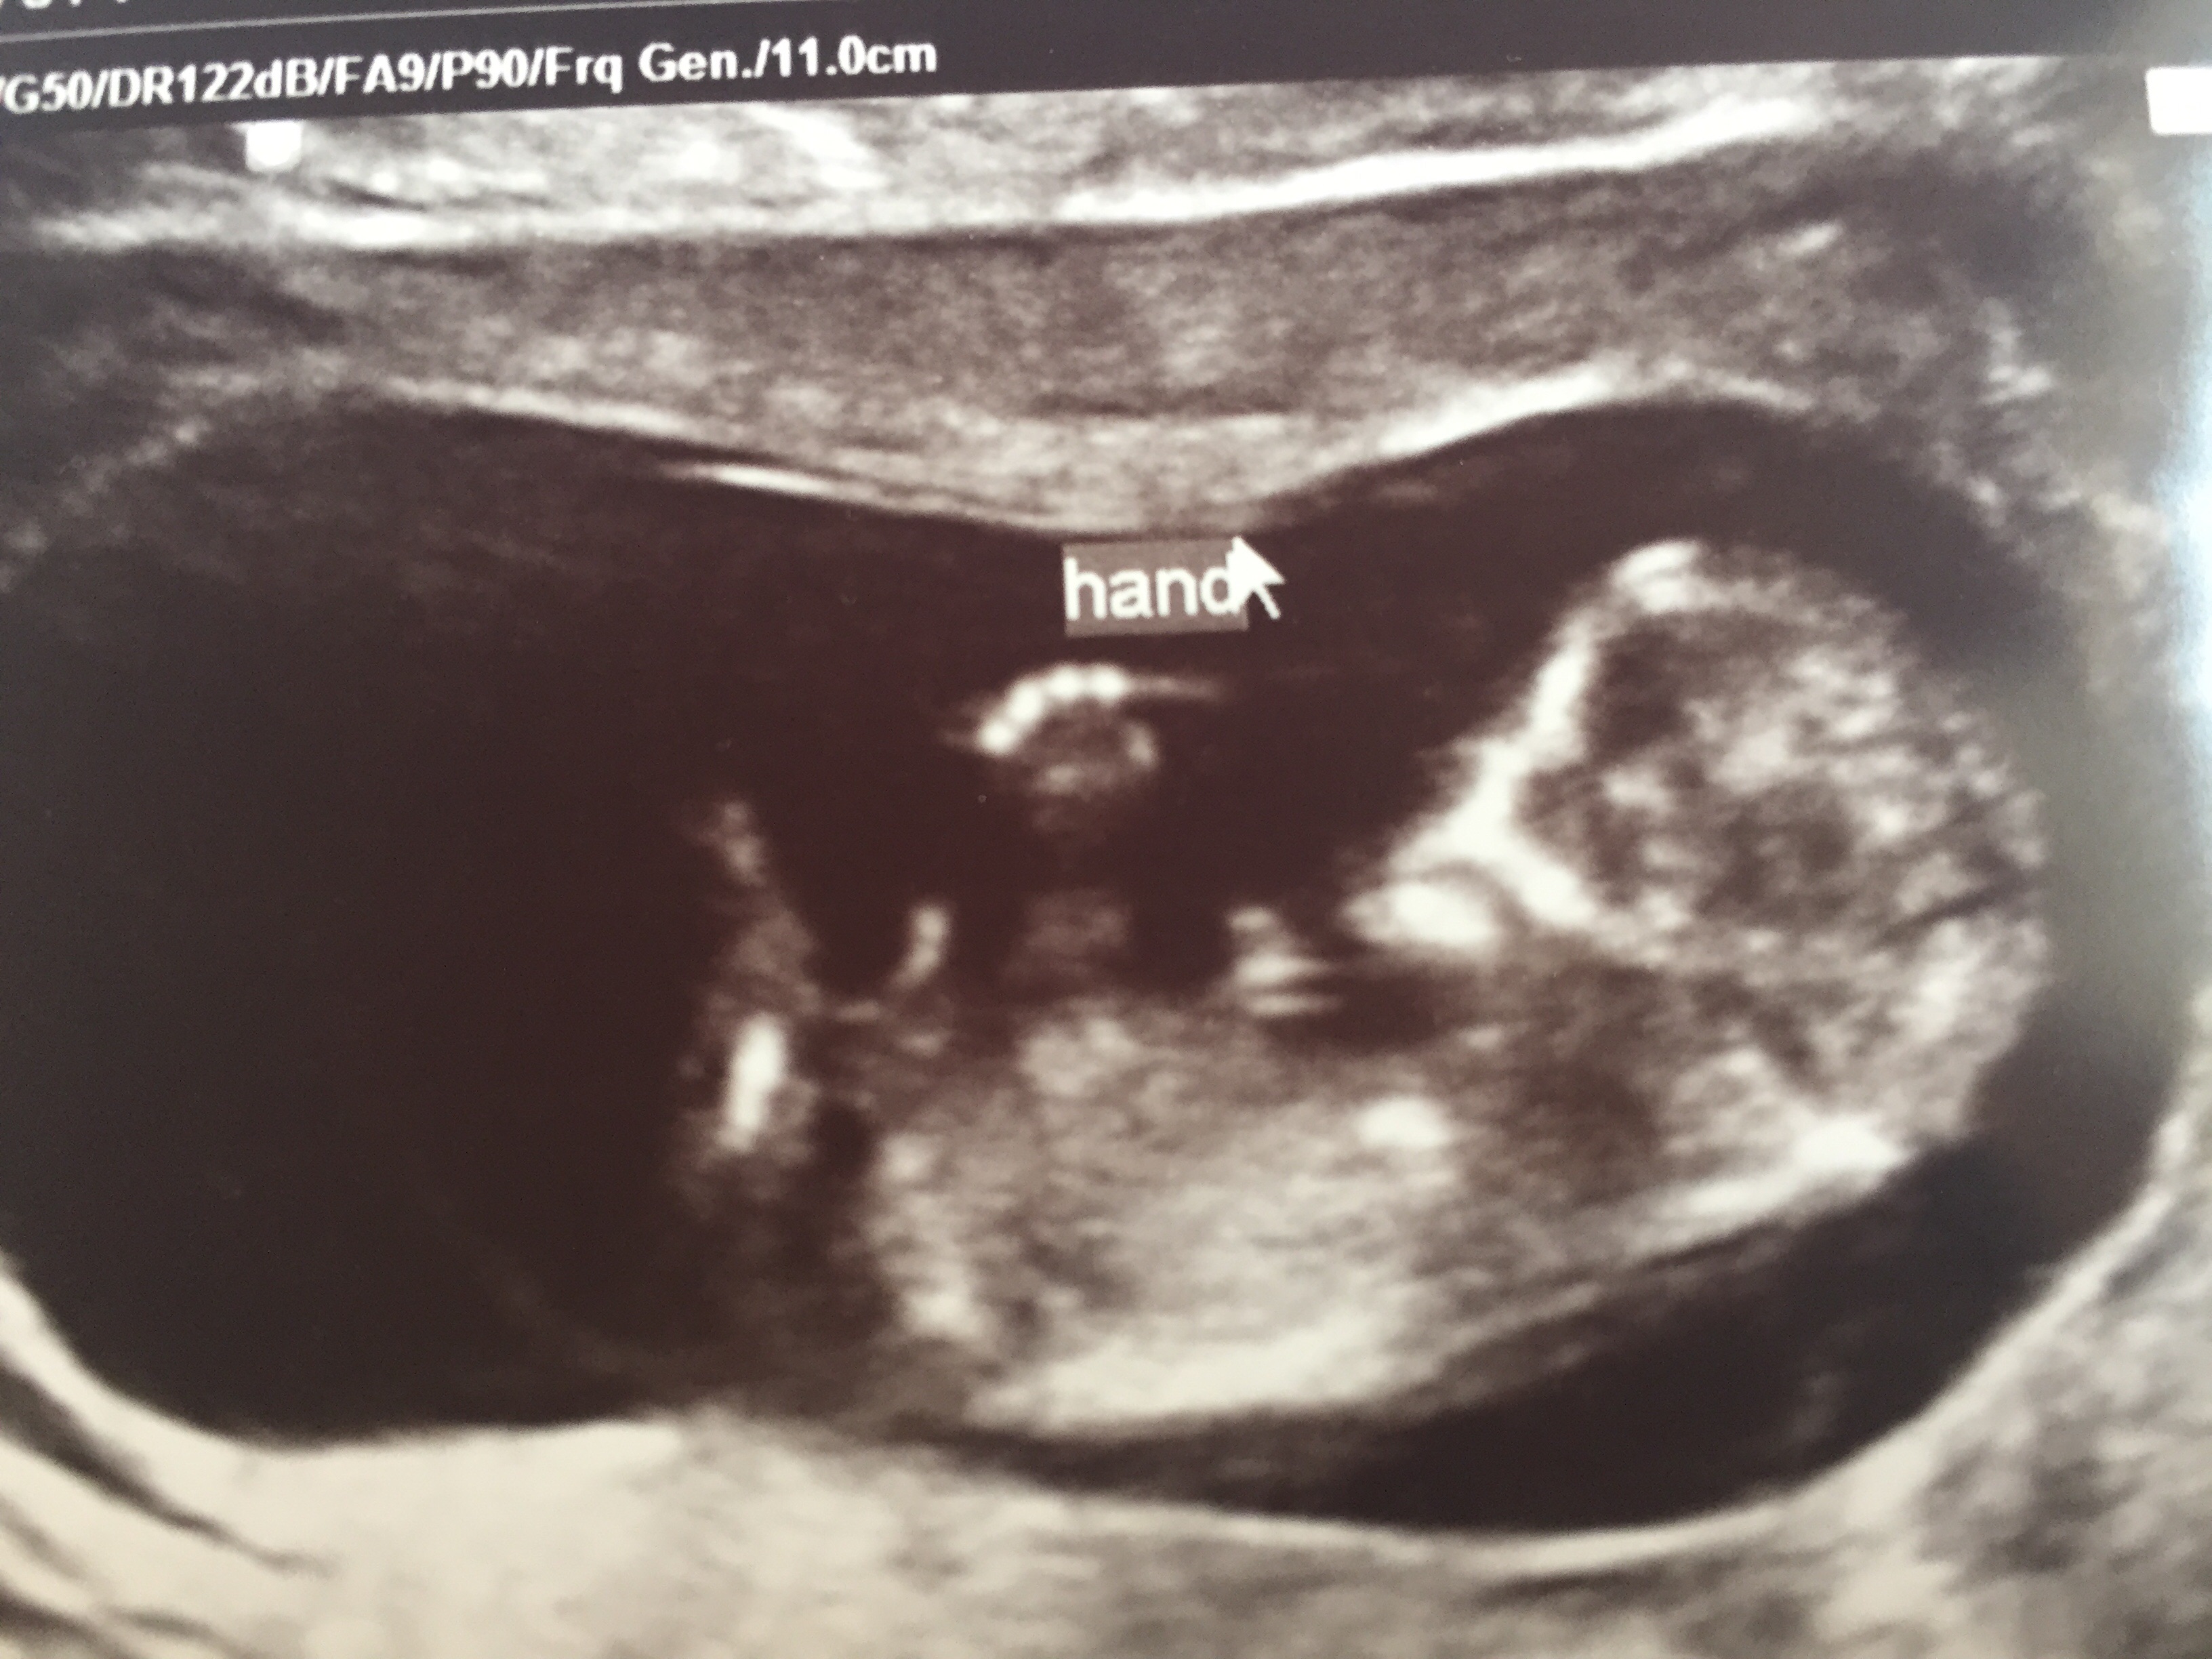

Here's our little guy or gal at 11 weeks, 2 days. NT test came back negative...feeling relieved! Baby was kicking and waving it's arms and hands around. So much fun to see our sweet baby!